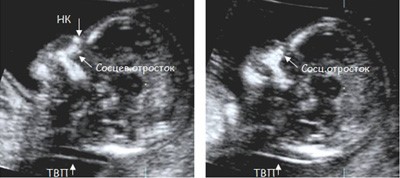

Для оценки этих признаков врач должен обладать высокой квалификацией, так как получение необходимых ракурсов плода в ранние сроки беременности требует опыта и технических навыков. Для измерения ТВП необходимо получить такое изображение:

На фото УЗИ беременной видна только голова и верхняя часть туловища плода, четко виден профиль, носовая кость и ТВП. Достаточно часто можно увидеть такие некорректные изображения:

На этих изображениях плод лежит криво, увеличение изображения недостаточное, нельзя увидеть четкий профиль плода. Измерение ТВП в таких изображениях НЕКОРРЕКТНО и приводит к завышению или занижению риска болезни Дауна!!!

Схема измерения толщины воротникового пространства